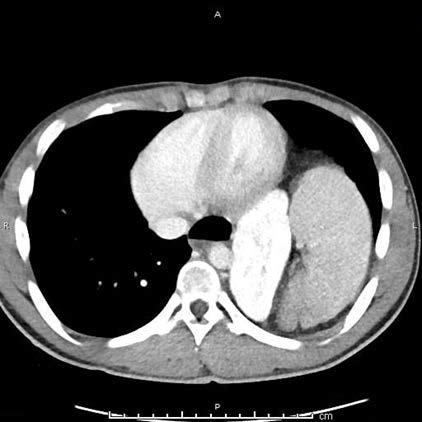

Left-Sided Bochdalek Hernia with Gastric Volvulus and Intrathoracic Kidney in a 21-Year-Old Male: A Case Report

Aneesh Kakkatt, Shahana Aneesh

1-7